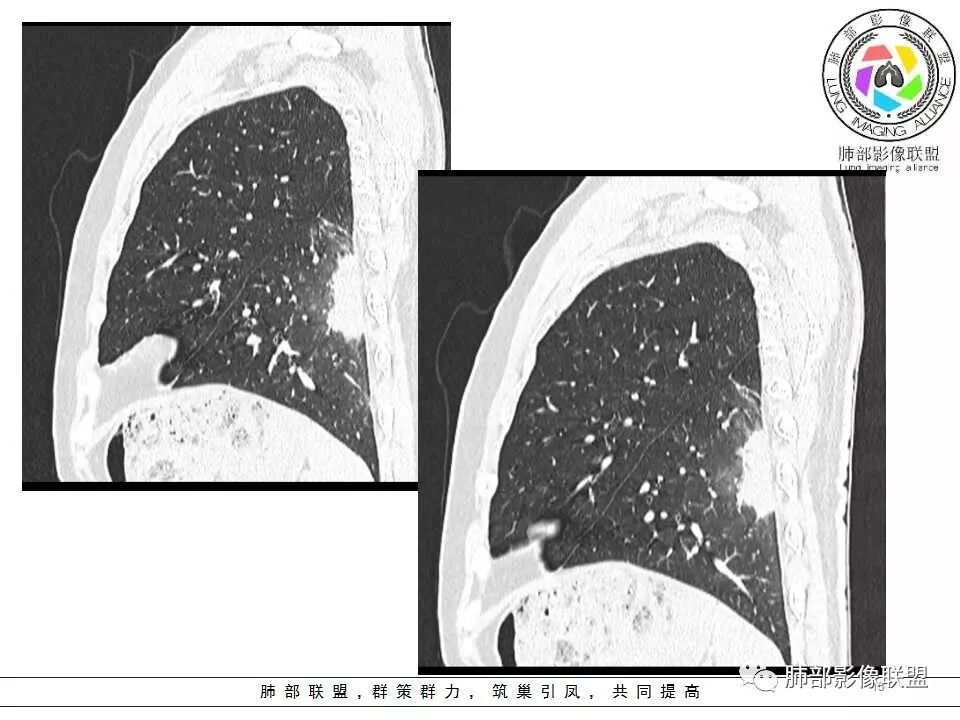

影像资料

左肺下叶实变,长轴与胸膜平行,边缘平直、膨隆,周围有边缘模糊晕,近端支气管进入病灶,內有低密度坏死,邻近胸膜弥漫性增厚,胸膜外间隙增宽;病灶周围肺野有多个斑片,部分内有扩张小支气管。青年男性,病史10天,考虑炎性,1、隐球菌,2、TB。

中年男性,咳嗽胸疼,左肺下叶团片状影,边缘平直,内有多灶坏死,胸膜下分布,与胸膜宽基底相连,周围有晕及晕中毛刺,有卫星灶,支气管进入走行自然,有的穿过,有的近中段阻塞,胸膜下脂肪间隙清晰,考感染性疾病,隐球菌肺炎可能性大,鉴别op。

青年男性,咳嗽,胸痛10天,白细胞不高,中性粒细胞不高,1月前有发热史,1年内体重下降10公斤,胸部CT所见左肺下叶跨背段及后基底段不规则形团块影,宽基底与胸膜相连,胸膜下脂肪间隙清楚(糊墙),长轴平行胸膜,内有坏死,边缘毛糙,周围见晕征,病灶旁有斑点状及小结节状影,病灶由外向内包绕支气管,考虑:炎性肉芽肿,隐球菌可能,结核待排,查隐球菌荚膜实验,必要时痰检及结核相关检查。

青年男性,咳嗽咳痰胸痛,有发热史,体重下降,结核抗体弱阳性。胸部CT所见左肺下叶跨背段及后基底段不规则形团块影,边界相对清楚,内部似见坏死,病灶沿胸膜下平行于胸膜横向发展,邻近胸膜增厚,周围见边界不清磨玻璃密度影。左肺下叶背段及后基底段近肋膈角区见多发较小形态及密度相似结节,部分结节周围见条索影。综合考虑炎性病变,隐球菌感染可能性大,建议查隐球菌荚膜实验,询问有无鸽子接触史等。